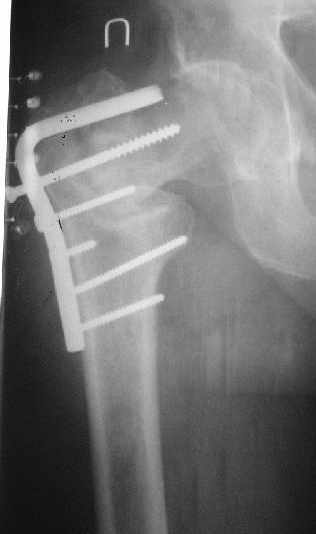

Дистракция позволит улучшить шеечно-диафизарный угол. Фиксировать технически проще пластиной, оптимально 130-градусной. Можно и с другим углом, только спланируйте тщательно, как должен быть направлен шеечный элемент, чтобы не оставить варус.

Гвоздем тоже можно, но технически труднее, надо вводить джойстики в шейку...

В приложении пример с гвоздем.